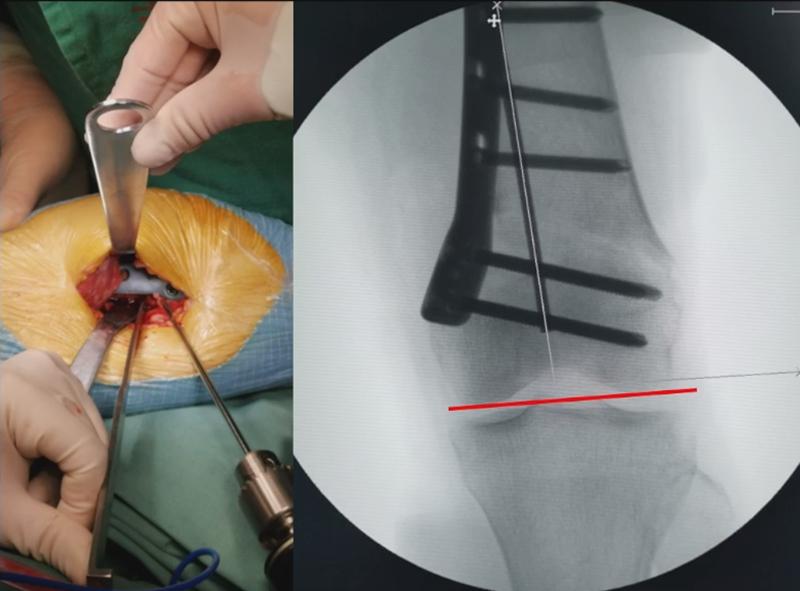

3、选择合页位置和截骨线

合页点的选择与HTO一样,通常需要尽可能接近畸形部位,既要有很好的骨质结构,还要有坚韧的软组织覆盖,以保证稳定性和术后有良好的血运。合页宽度不宜太长,通常保留在5mm。

合页点定位有两种方法,一种为定位在股骨外后髁上缘2mm位置,通常将此区域叫做“鹰嘴区”,以此为解剖标记法来定位合页点。

另一种通过导针从截骨入点向股骨外后髁后缘打出一条切线,此切线与外侧骨皮质的交点,也可作为合页点,这种方法称为导针法。这两种方法在手术之中是可以互为验证的。

合页点和截骨线已确定好,按照术前计划打入导针,测量截骨深度。

水平截骨时,同样放肢体中立位,后侧放一把骨撬保护后方重要结构。

截骨过程中,不要求一次截骨到位,把合页深度全部截到,可以留最后一点,用钻头由前向后打出一排筛孔来,把合页端弱化,再去做闭合时就不容易折断了。

然后核实力线,如力线位置良好,就可以采用内固定的方式将位置维持好。